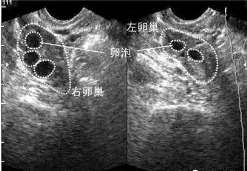

卵泡监测

B超检查